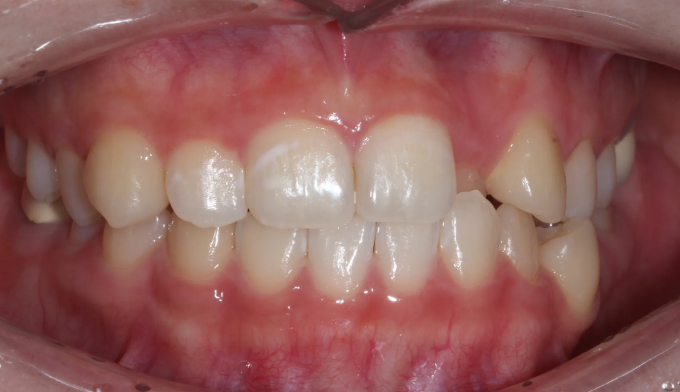

덧니,

돌출입

10대

2025.02.11